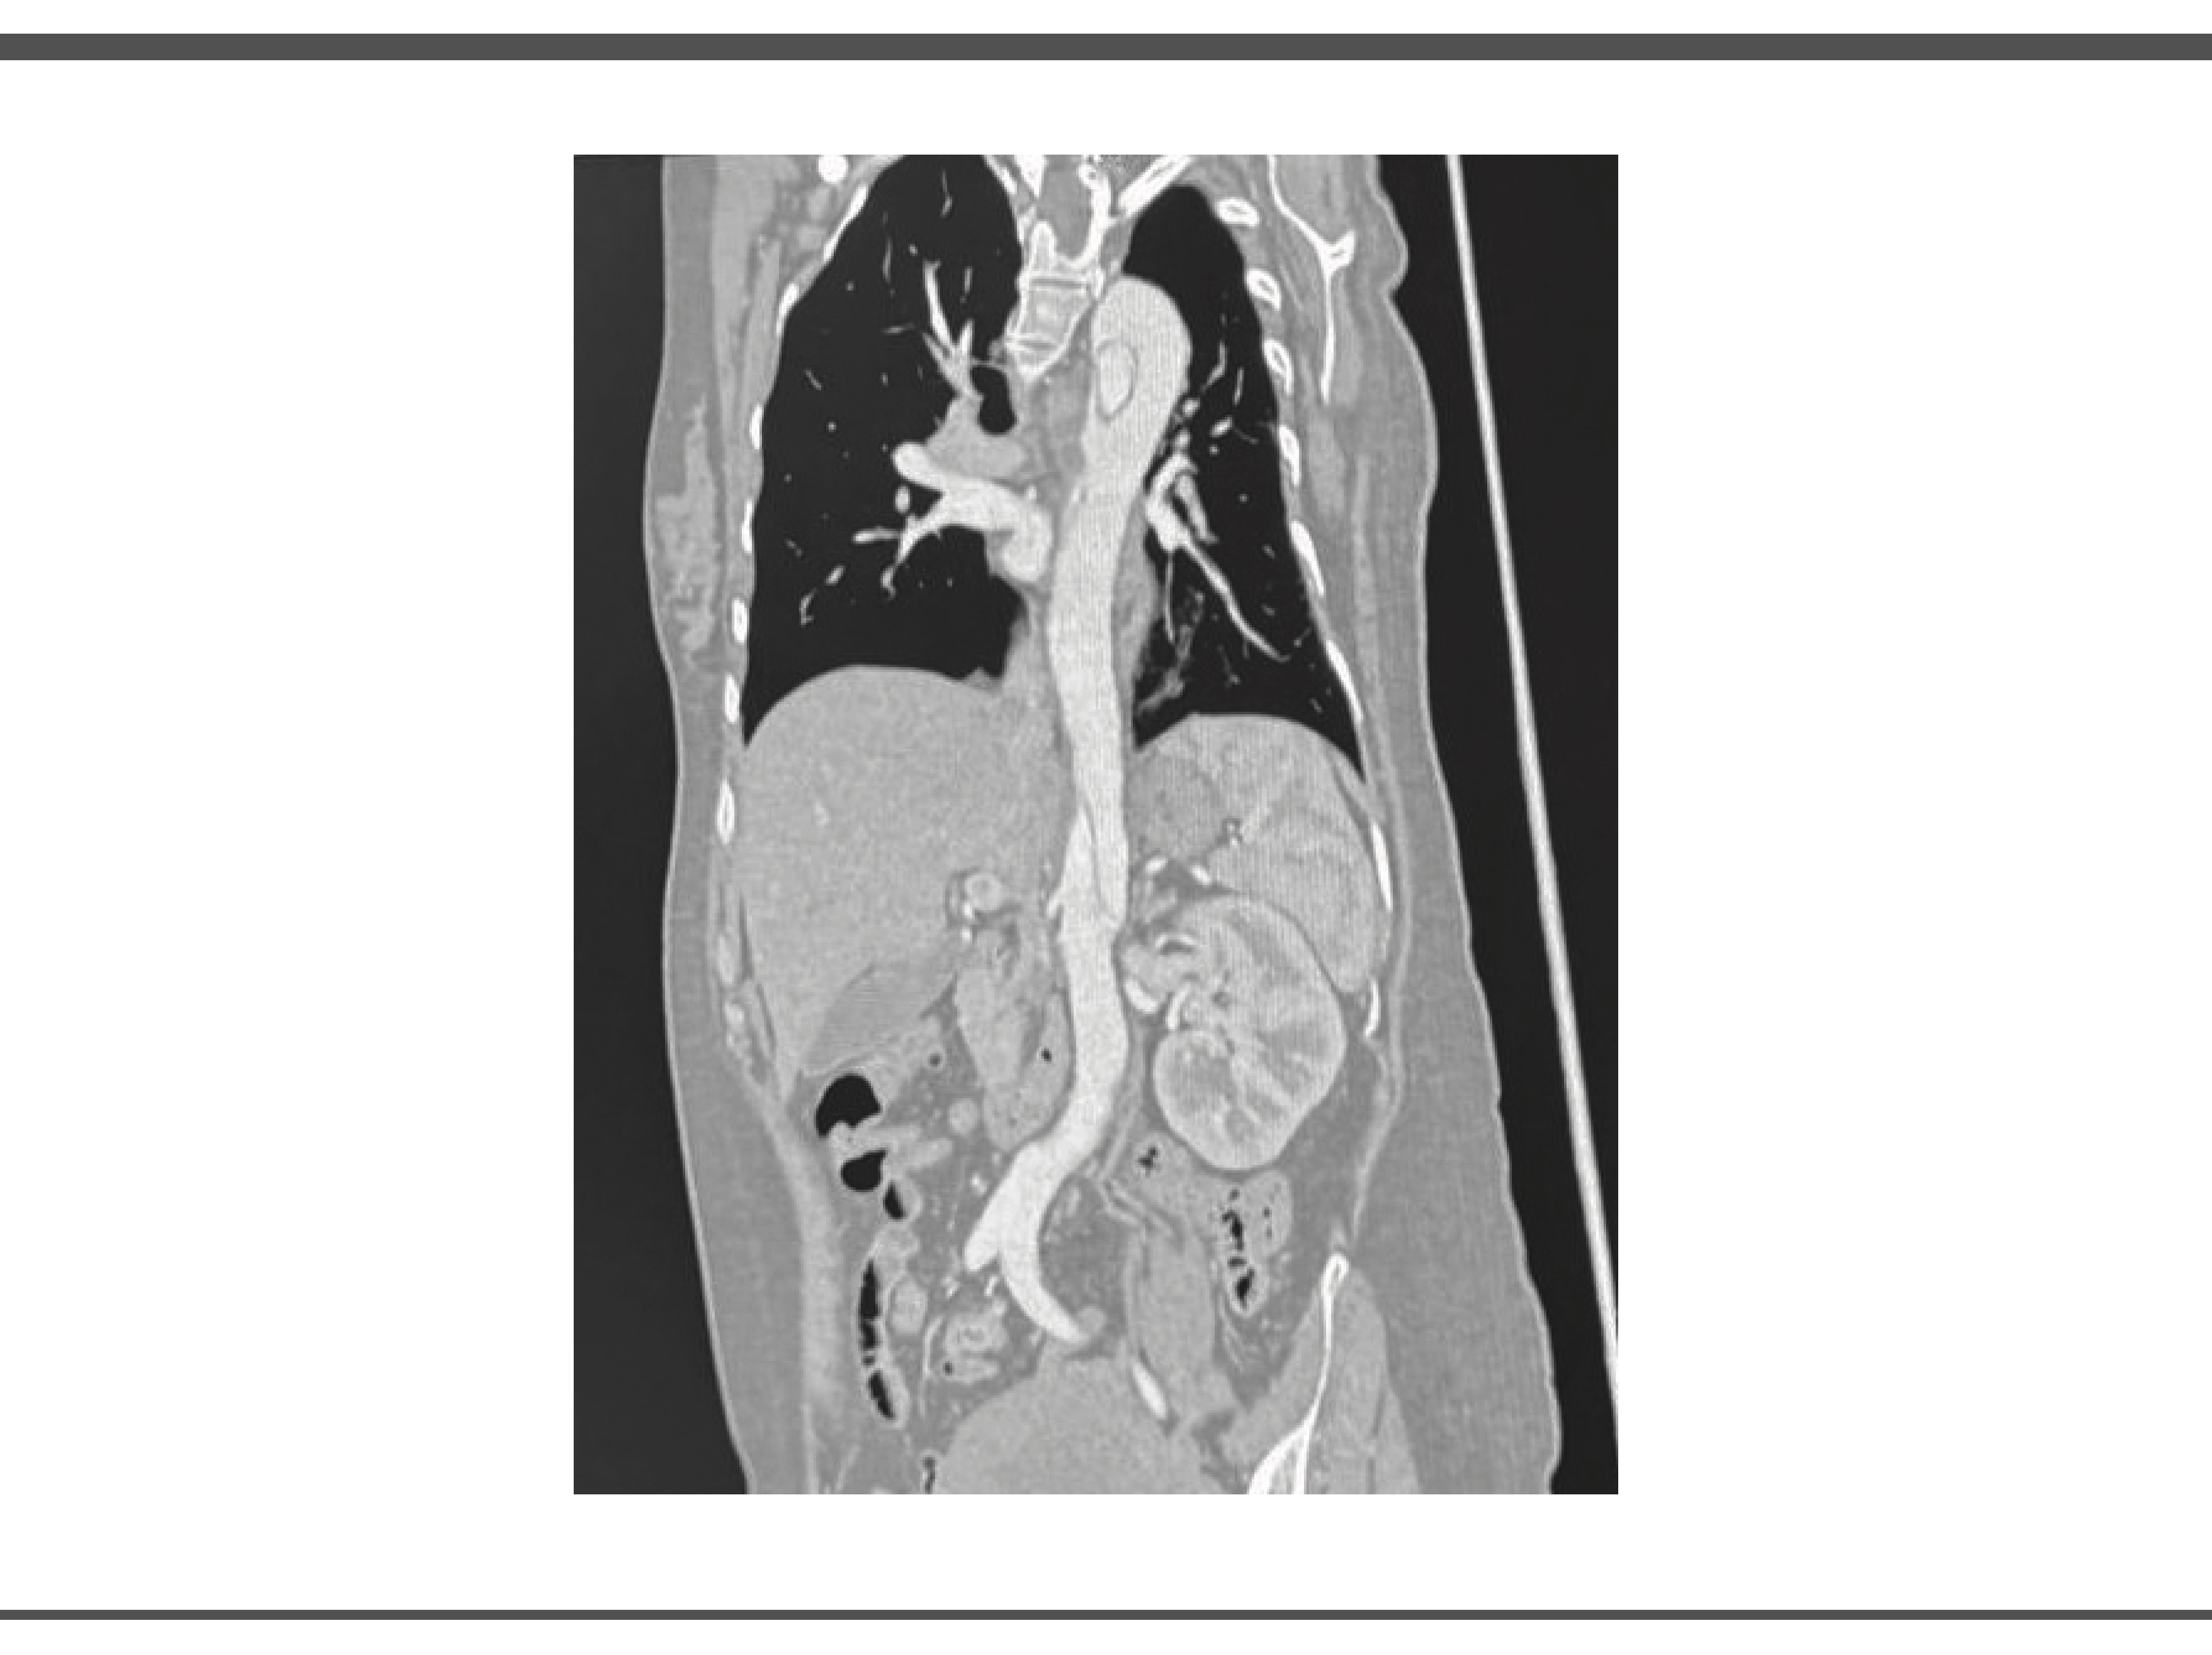

Durante su estancia en UCI se realiza angiotomografia en donde se obtienen imágenes compatibles con disección aortica, así como valoración por el servicio de angiología y cirugía vascular en donde se observó arco aórtico tipo II, con disección inmediatamente posterior a ostium de arteria subclavia izquierda, con extensión observable en ultimo corte en la aorta infrarenal con ramas viscerales dependientes de luz verdadera, por lo que la paciente es candidata a exclusión endovascular de segmento torácico y viscerales, pero debido a ausencia de insumos endovasculares y capacidad resolutiva, no es posible realizar este procedimiento en nuestro hospital. (Ilustración 2 y 3)

IMAGEN 3.

Fuente: Expediente de paciente. Fecha Marzo 2025